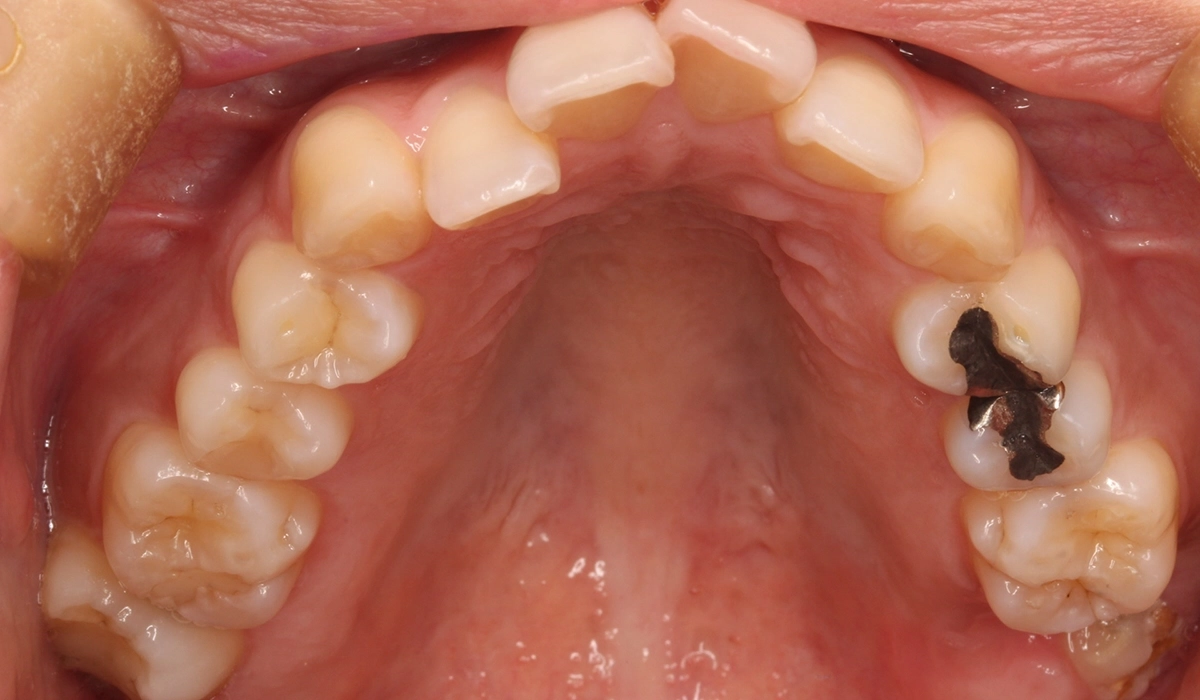

術前:上顎

術前:上顎前歯部寄り

今回ご紹介する患者様は、上下前歯部のがたつきを気にされており、検査後Ⅰ級叢生と診断いたしました。左上7番予後不良により抜歯し、左上8番を配列したためやや治療期間が長くなるも満足いく配列となり患者様も満足していただけました。

| 治療内容 | 上下前歯部のがたつきを気にされており、検査後Ⅰ級叢生と診断いたしました。左上7番予後不良により抜歯し、左上8番を配列したためやや治療期間が長くなるも満足いく配列となり患者様も満足していただけました。 |